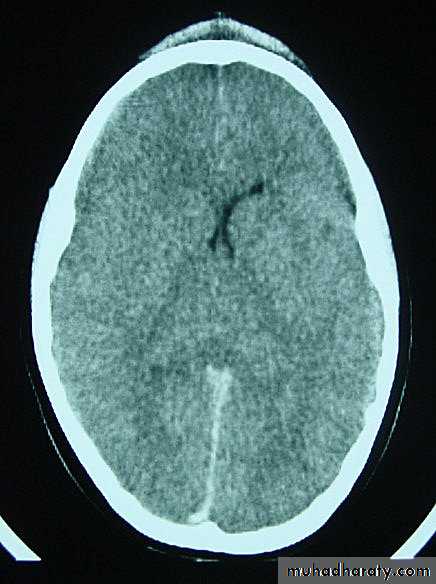

c. Intracerebral Haematoma

This is the least common of traumatic haematoma.

They are due to areas of traumatic contusion coalescing into a contusional haematoma.

Disrupted cerebral tissue release thromboplastins that potentiate haemorrhage.

CT scan: appear as hyperdence lesions with associated mass effect and midline shift.

Large intracerebral haematomas should be evacuated unless the patient’s neurological state is improving.

Small inracerebral haematomas may not require removal, but be aware that they can expand.